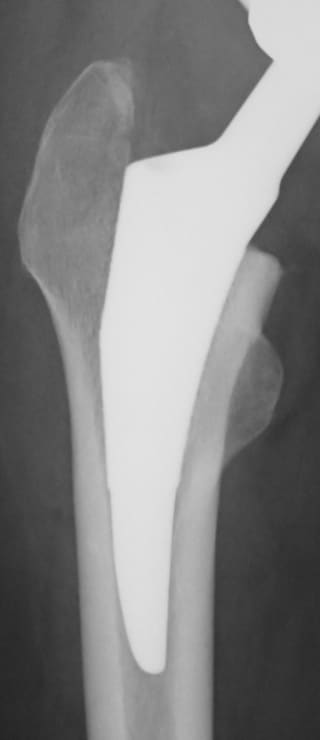

人工股関節置換術は英語で 「Total Hip Arthroplasty」「Total Hip Replacement」と表記され略して「THA」や「THR」と呼ばれています。人工股関節置換術とは、傷ついた股関節の損傷面を取り除いて、人工の関節に置き換える手術です。

手術では、まず皮膚切開し、筋肉を分けて関節を開いて大腿骨の骨頭を取り出します。続いて寛骨臼の損傷面を取り除き、金属およびポリエチレンでできた人工股関節に置き換えます。

人工股関節置換術の方法は、骨とインプラントをどのように固定するかによって大きく2つの方式に分けることができ、ひとつは骨セメントという固定材料を用いる方法(セメント人工股関節)、もうひとつは骨セメントを用いずに骨とインプラントの直接結合をめざす方法(セメントレス人工股関節)です。

世界の動向としては、人工関節技術が発展を始めた当初の1970年代から1980年代にかけてはセメント方式が主流でしたが、1990年代から2000年代へとセメントレス方式が大きく見直されて主流となり、今日では本邦で行われている人工股関節の75%以上がセメントレス方式で行われています。

フラット

テーパーステム

ショート

タイプステム

モデュラーステム

セメント再建